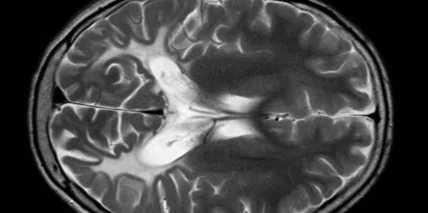

Мозок злочинців та людей, які мають кримінальне минуле, виглядає інакше! Таке відкриття дослідників підтверджує МРТ злочинців.

Люди, які брешуть чи знущаються з інших, мають меншу площу поверхні кори мозку. Дослідники виконали МРТ сканування семи сотням учасникам експерименту, за якими спостерігали від народження, пише Lancet Psychiatry.

Зокрема, 80 учасників останньої групи, до якої належали ті, що вчиняли насильницькі злочини впродовж всього життя, мали суттєві структурні відмінності мозку, а люди, які ображали інших, мали психоневрологічні відмінності.